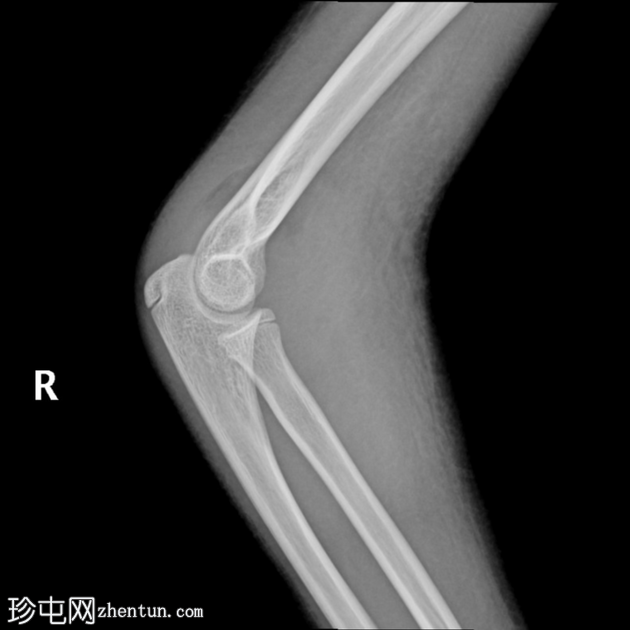

X线片

3.png

正位片

4.png

侧位片

两个投照角度均显示肘关节复位良好。

复位后,骨碎片被明确识别为未完全骨化的内上髁骨折。

肘关节内仍有积液。